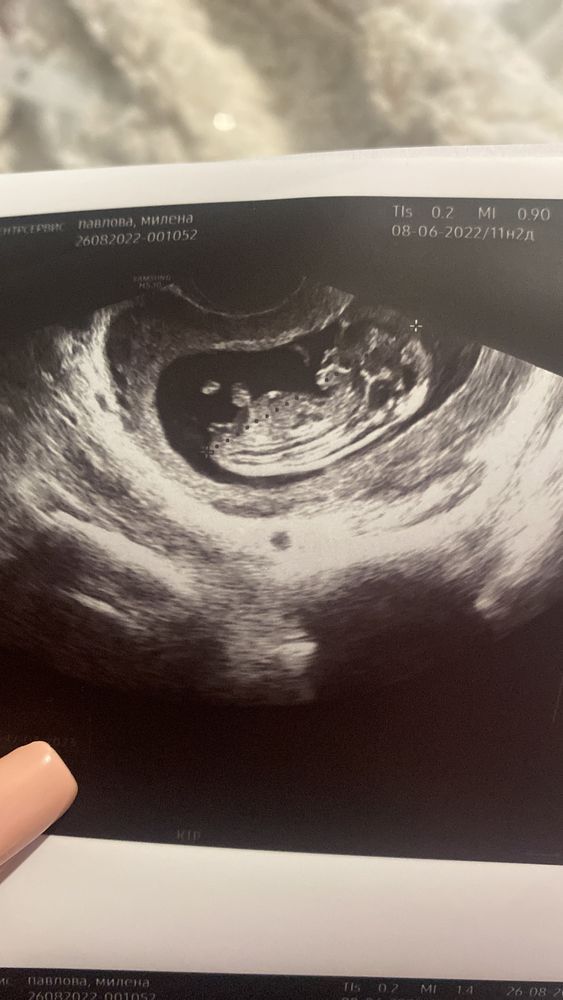

Видно ли пол ребенка по узи

Девочки, видно ли на узи пол ребёнка?) Увеличен кровоток в правой маточной артерии